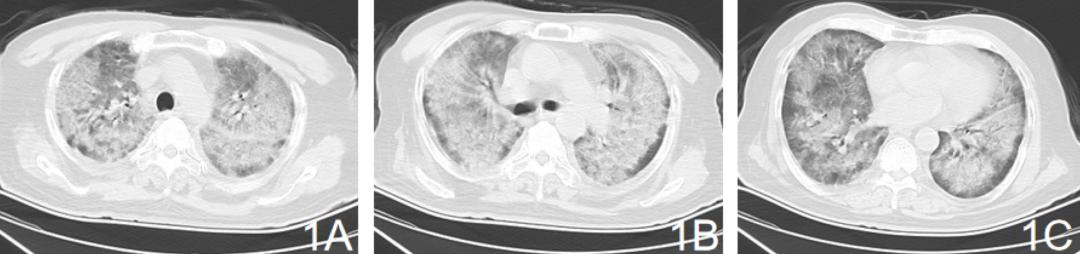

胸部CT:双肺弥漫性磨玻璃影及新旧不一的实变影,可见支气管气相【图1ABC】。

【图1】2020.3.14双肺弥漫性磨玻璃影及新旧不一的实变影